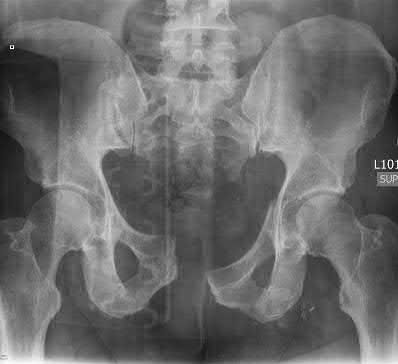

Question 1

A 45-year-old male sustains an anterior-posterior compression (APC) type III pelvic ring injury following a crush injury. He is hemodynamically unstable upon arrival. If an arterial source of bleeding is identified on pelvic angiography, which of the following arteries is most likely to be injured based on the fracture pattern?

Explanation

In anterior-posterior compression (APC) injuries, the internal pudendal and obturator arteries are the most commonly injured arterial branches due to disruption of the anterior ring. Conversely, in lateral compression injuries and fractures extending through the greater sciatic notch, the superior gluteal artery is the most frequently injured.